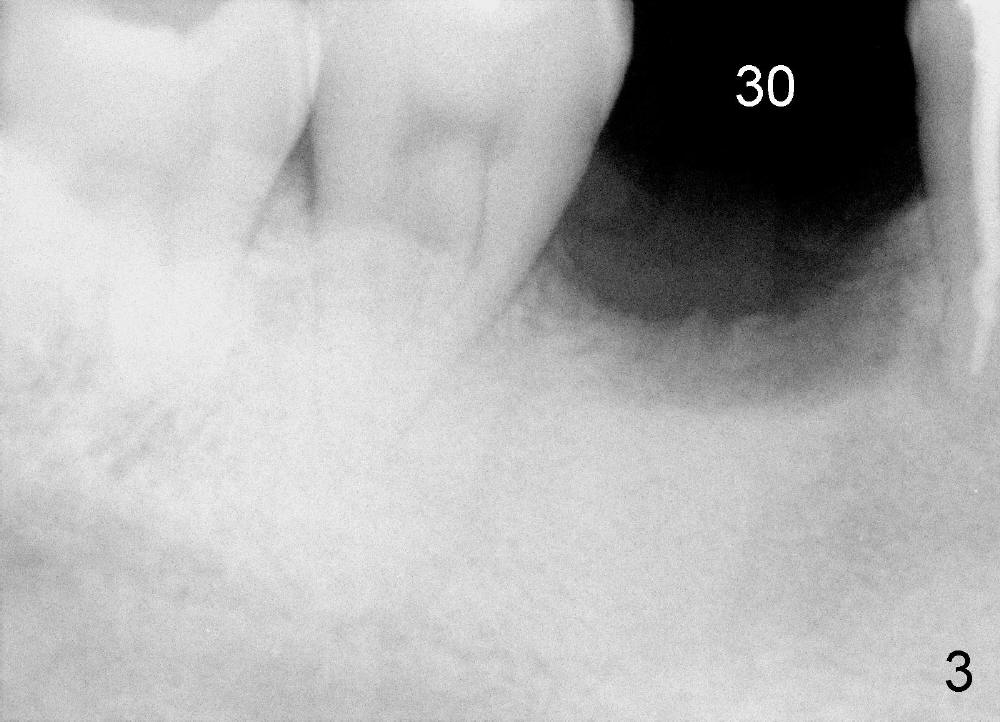

A 46-year-old man has severe periodontitis. The tooth #30 is complicated by incomplete root canal therapy (Fig.1,2). Three months after extraction (Fig.3-5: N: inferior alveolar canal), a 5x14 Tatum tapered implant is placed (Fig.6,7). The problem is that an implant driver is fractured (D in Fig.7), while the implant is being torqued. It takes time and effort to remove the fractured driver, but the implant is solid. The healing screw is placed without difficulty (Fig.8). Since the implant is placed lower than the lingual gingiva (L in Fig.9), a healing cuff is placed 1.5 months after implant placement (Fig. 10 and 11: C) to push the lingual gingiva down. The X-ray appears to show lower bone density around the implant (bone necrosis?), although the implant has no mobility at all. Since the implant is so solid, can we load it, two months after surgery? The lingual gingiva is now lower than the healing cuff (not shown). CT is scheduled to be taken tomorrow. Thanks.